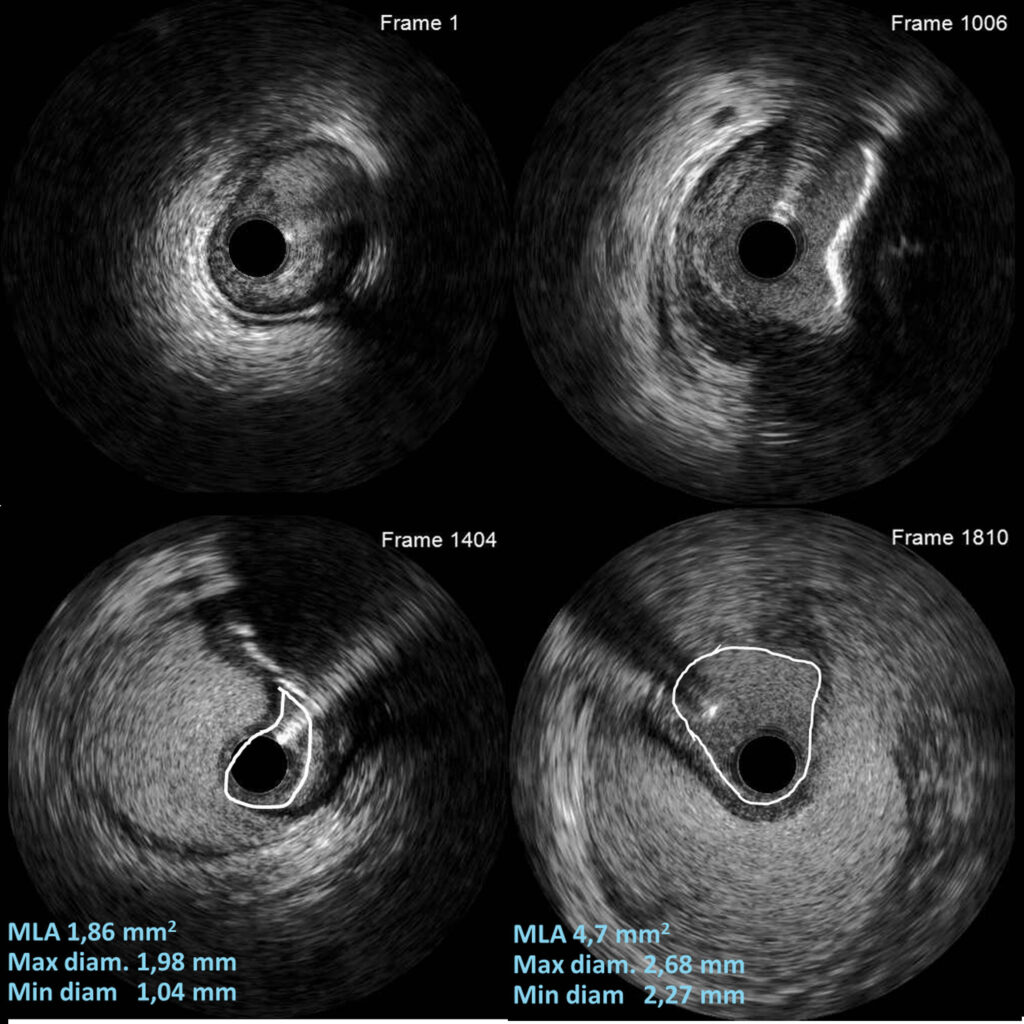

We analyze both quantitative and qualitative your IVUS, OCT and angiograms for your  research projects using licensed dedicated software.

We can provide clinical interpretation reports and measurements of your IVUS and OCT acquisitions. (like a radiology report of an X-ray picture).